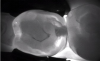

As an adjunct to 2-dimensional digital radiography systems, the use of 3-dimensional radiographs can present an attractive option. A CBCT system can be used to produce a 3-dimensional image to enhance or augment diagnostic capabilities.3 While adherence to the ALARA (as low as reasonably achievable" principle for all ionizing radiation modalities is the clear best practice to minimize patient radiation exposure, CBCT units impart doses approximately the same as 2-dimensional digital units, and indeed all digital imaging technology for oral healthcare produce far less exposure than medical CT units.3 When used as appropriately indicated, both 2-dimensional and 3-dimensional digital radiographic technology provide practitioners access to oral and maxillofacial information that can be beneficial in the diagnosis of osseous degradation, root pathologies, fractures, and pathologies, as well as the aforementioned capacity to expand into implant surgical, orthodontic, or endodontic procedures.3-5

Transilluminating technologies emit light at the base of the tooth at the gingival area and transmit light up through the tooth. At the applied wavelength, enamel starts to absorb fewer photons and water starts to absorb more photons, so lesions appear as dark areas on a monitor.6-8 This visualization can be helpful not only for the clinician to identify and diagnose problematic areas (Figure 1), but it also allows patients to see all aspects of their mouth including their cheek, tongue, and tooth, as well as the areas that have decay, thereby potentially assisting in case acceptance.

Transillumination can be used in interproximal, occlusal, and anterior surfaces.5 In many cases the technology is able to show how expansive the decayed area is on occlusal areas that may only have a minimal pit that would not allow a probe to be used (Figure 2 through Figure 4). Visualizing the interproximal regions of posterior teeth is possible as well although this may require a specialized fiber-optic tip.6